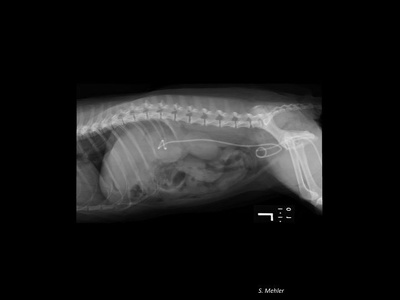

気管ステント術

気管虚脱や気管腫瘍などで気管が狭窄してしまった場合におこなうステント術です。気管ステントも透視下でおこなうため全身麻酔は必要ですが、切開などは必要なく30〜1時間で終了します。